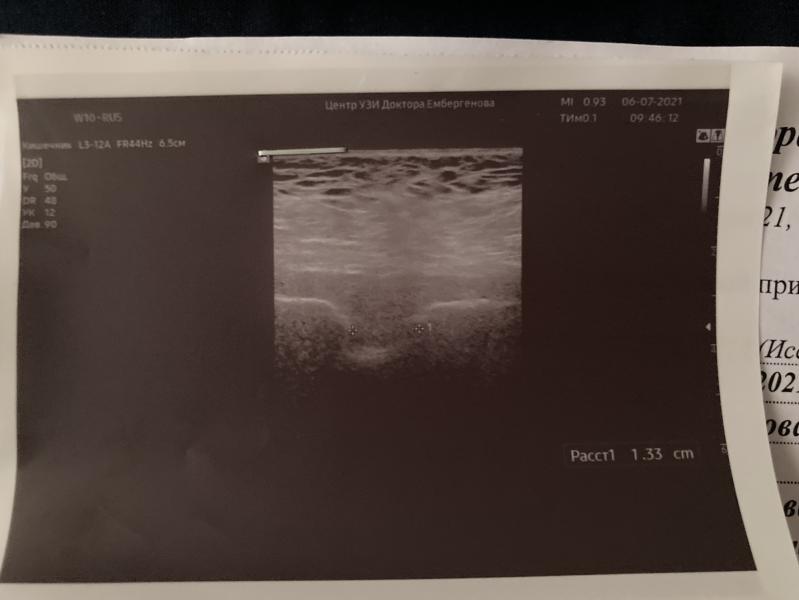

Ну чо, сходила на узи к Боренштейн, расхождение лона 1,33см 🤦🏻♀️

Завтра начинается 38 неделя, а малышка по всем параметрам на 39-40 недель, даже выходит за пределы параметров🤷🏻♀️ лежит ооочень низко, голова уже почти в тазу🤬 примерный вес на сегодня 3800😩

Гинекологу выслала узи на вотсап, позвала на приём в четверг, сказала направит на кс, теперь переживаю, как бы малышка не опустилась в таз, и не начались схватки…